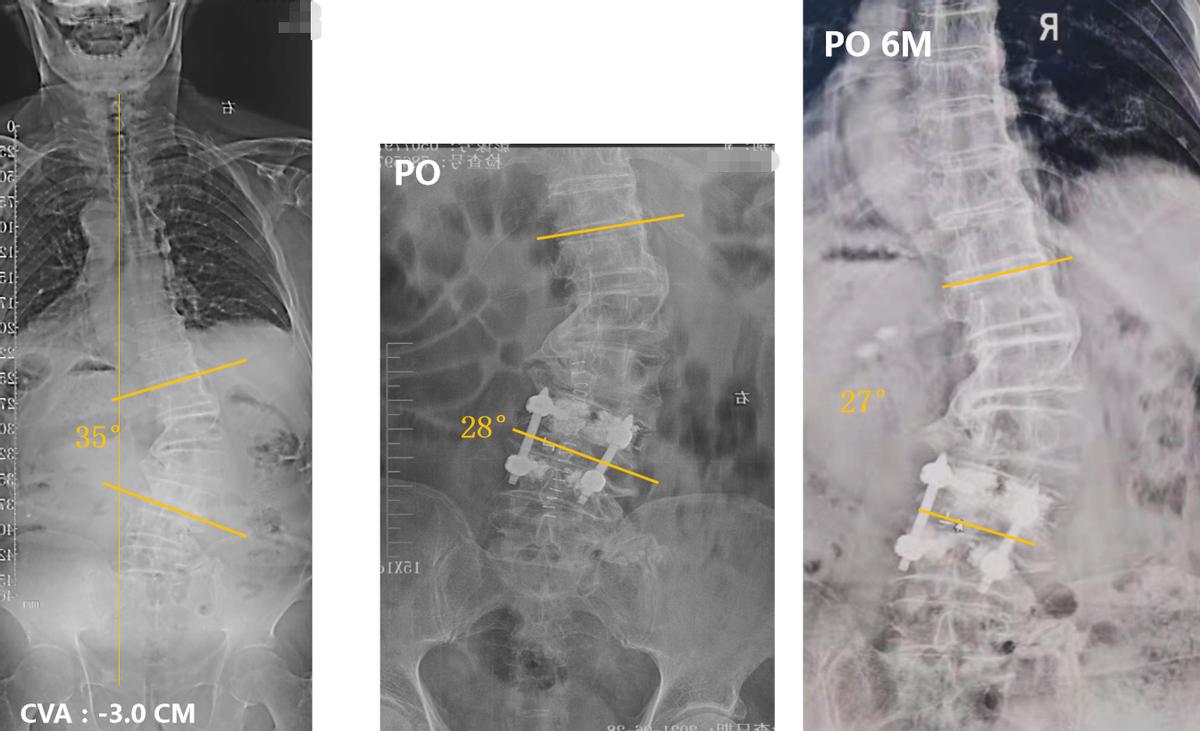

从患者的X线片可见,腰椎 35度右侧凸,顶椎L1/2。冠状位整体平衡还可以。矢状位:SVA 15.0CM。LL 20°。患者主诉病情加重前,无身体前倾等失平衡表现,腰痛引起异常体位。因此,我们判断患者的脊柱侧弯属于 Lenke-silvia III型 ADS。

由于患者Cobb角在30°左右,廖博主任团队决定进行“责任节段+X”短节段固定。为了精确责任节段,给患者进行了L5神经根选择性阻滞,原有症状没有诱发和缓解。因此,排除L4/5,将责任节段明确定位到L3/4。最终治疗方案决定为进行 L3/4的TLIF手术,钉道强化,L3椎体强化,术后进行长期的抗骨质疏松治疗。

术后影像学资料: